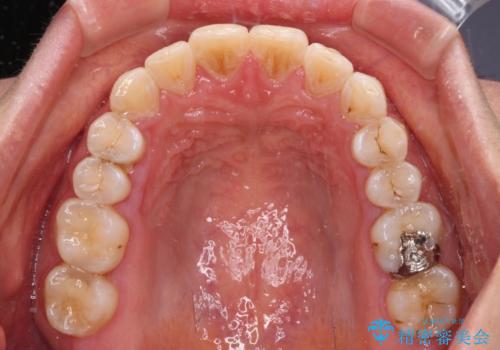

前歯の捻れを改善 インビザラインによる矯正治療

- 前歯の翼状捻転を気にして来院された患者様です。

全体的に叢生は軽度であったため、インビザラインにて矯正治療を行うこととしました。

前歯の幅の大きさも気になっていたため、IPRにより叢生を解消するとともに、歯の大きさも改善しました。